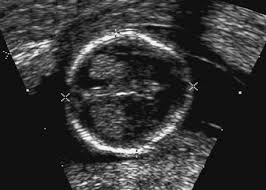

Nuchal Translucency And Other First Trimester Sonographic Markers Of Chromosomal Abnormalities American Journal Of Obstetrics Gynecology